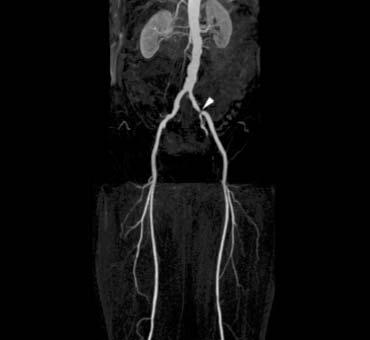

Ở những bệnh nhân này, nhiệm vụ của MRA là tìm các động mạch còn thông ở cẳng chân hoặc bàn chân để phẫu thuật bắc cầu có hoặc không kết hợp nong mạch qua da (PTA).

Cần nỗ lực tối đa để tìm các mạch máu ở cẳng chân và bàn chân, vì nếu không tìm thấy động mạch nào, việc cắt cụt chi sẽ không thể tránh khỏi trong hầu hết các trường hợp.

Cần thực hiện quy trình chụp hai bước. Đầu tiên, tập trung vào cẳng chân và bàn chân với độ phân giải không gian tốt nhất có thể. Tiếp theo, chụp vùng chậu và đùi. Hiện tượng ngấm thuốc tĩnh mạch từ lần chụp đầu tiên thường không gây vấn đề ở các vùng này.